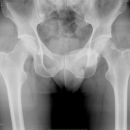

Fraktur Ramus pubis sup. und inf.